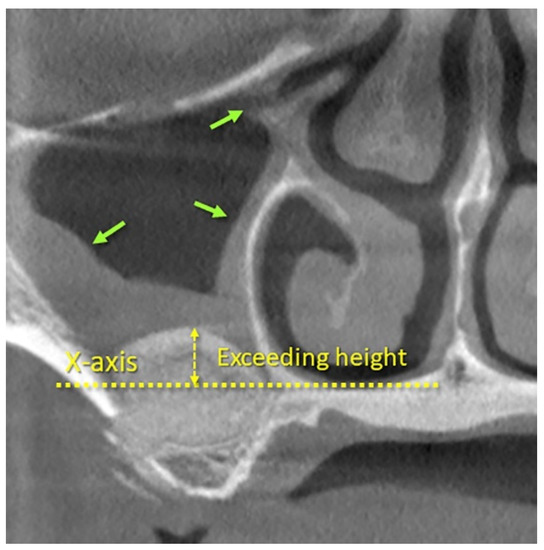

| EH | Exceeding height at X-axis | 1.6 ± 3.5 | −0.1 ± 3.3 | 1.7 ± 2.0 | |||